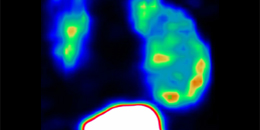

Strategy for tracking and quantifying immune cells with PET© CRC inSight Targeting immune cell dynamics by longitudinal wholebody imaging and mathematical modelling